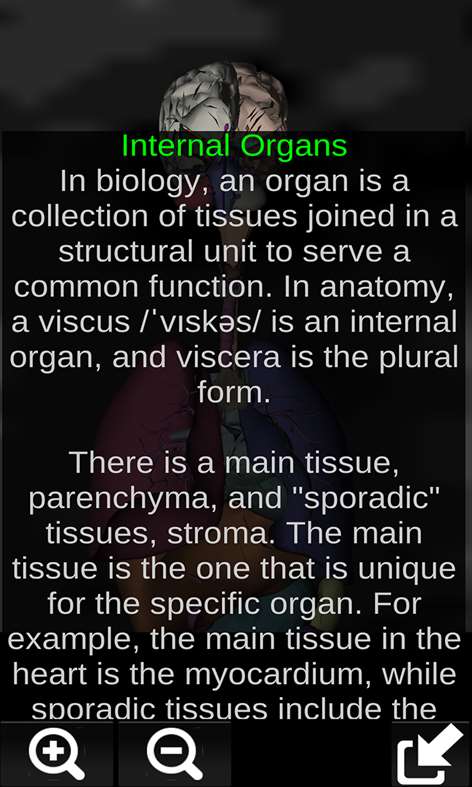

Shows a three-dimensional model of the human body organs and a description of all of them. This application is intended to complement the study of anatomy in medicine, biology or other. Touching each organ as the heart, brain, lungs, reproductive system, liver, intestine, ovary, testis, stomach, kidney, etc.. information is displayed. Practical, useful and valuable anatomical information in your palm. Reference to primary education, secondary school, college or culture in general.